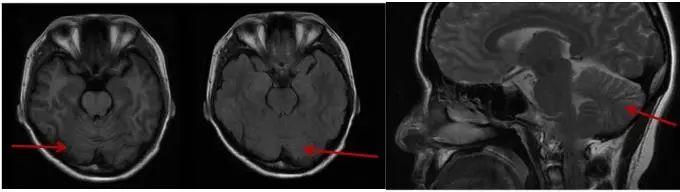

1.2 家系调查 见家系图谱(图3),先证者之父约70岁发病,症状相似,具体无法追溯,因他病亡故。先证者之女尚无临床症状,头颅MRI小脑无明显萎缩(图4),查基因检测提示CACNA1A CAG重复次数为 22 次(图5),在全突变范围内。

图4 患者之女MRI T1、T2及矢状位图Fig.4 MRI T1, T2 and sagittal maps of patient’s daughter, 2023